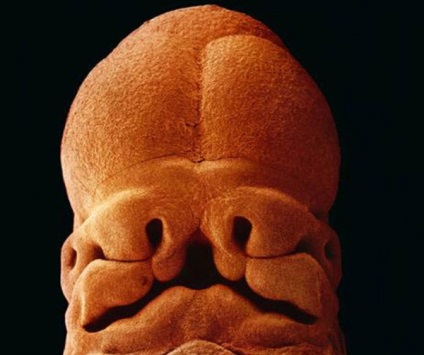

Ziua 22 a dezvoltării embrionare. Materia cenusie - este viitorul creier

28th zi după fertilizare

5 săptămâni, lungime de 9 mm, deja ghicit fața cu găuri pentru gura, nările și ochii